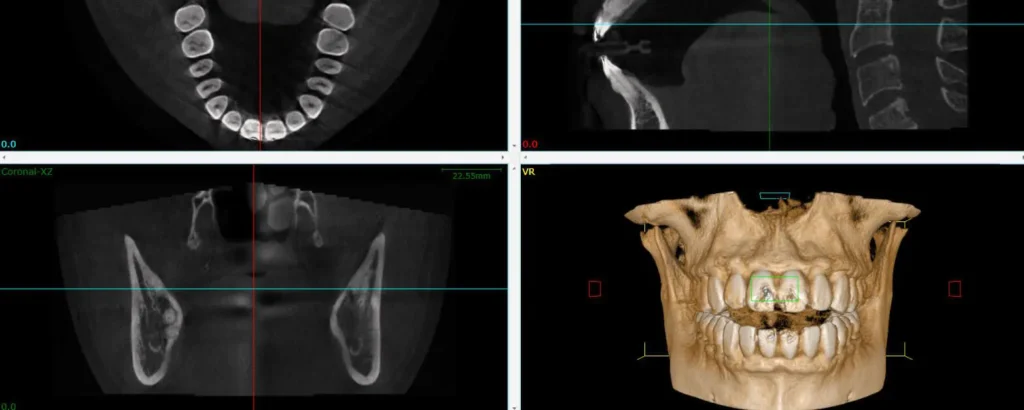

Seeing Inside The Bone With A 3D Cone CT Scan

A cone beam CT creates a 3D view and cross sections of the target area. The information it provides is critical for a number of situations, including placing dental implants, performing a complex root canal or extraction, or searching for the source of pain or infection. CBCT gives us the information we need about your condition before a dental procedure.